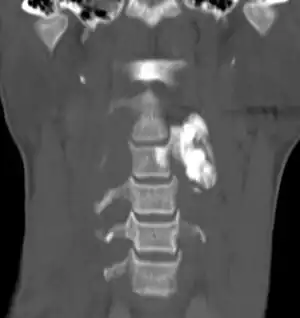

Type Name Sub-type Image

Non-cancerous Osteoma

Osteoid osteoma

Locally aggressive Osteoblastoma NOS